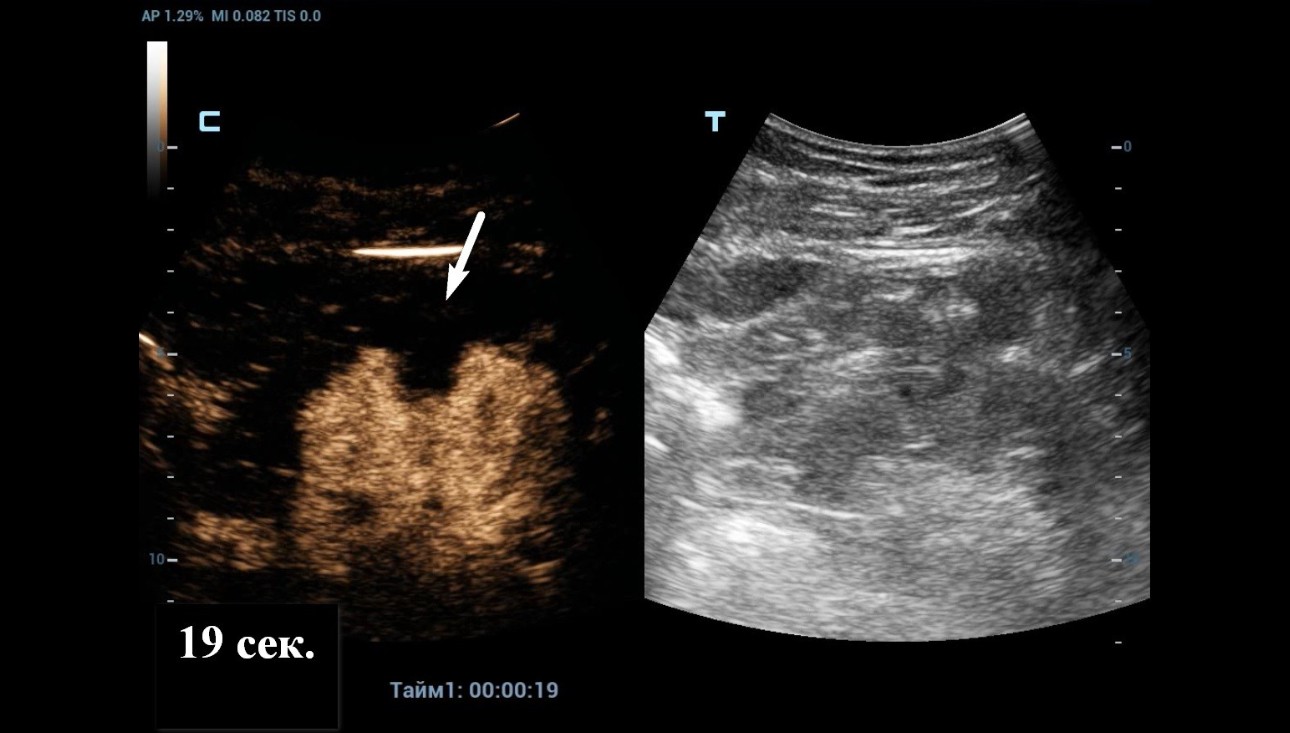

2) Contrast Enhanced Ultrasound (CEUS)

As Power Doppler showed indeterminate results regarding internal flow within the complex cystic mass, CEUS was performed through injection 1.2 ml of Sonovue (Bracco Swiss, SA, Switzerland). The longitudinal plane of the kidney with the maximum section of the cystic mass was selected for scanning. At the end, the cystic mass was characterized as benign by a lack of enhancement throughout the CEUS study (Figure 4 and 5).

Figure 4: CEUS imaging of the kidney at 19 seconds post injection.